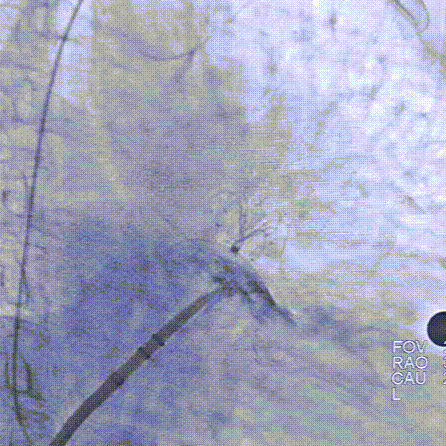

LAMax LAAC®2436 Plus封堵器封堵盘在DSA下牵拉15s,锚定伞稳定无移位。

牵拉实验,牵拉稳定无残余分流